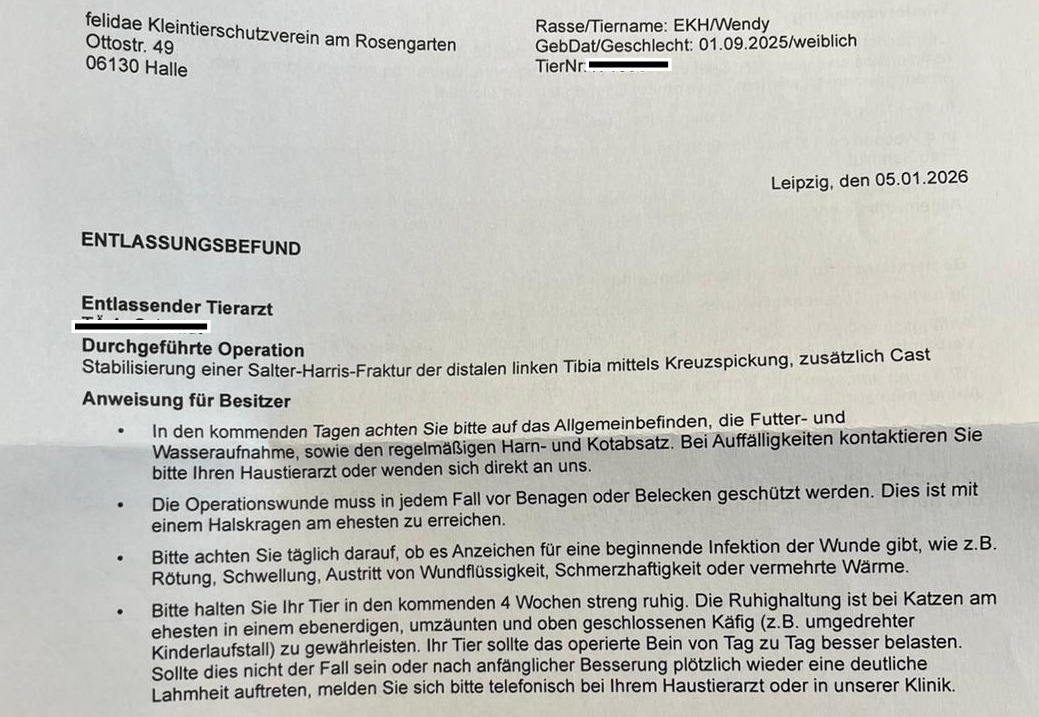

Salter-Harris-Fraktur (Wachstumsfugenbruch) am linken Hinterbein.

Wendy wurde umgehend in die Tierklinik Leipzig überwiesen und dort operiert. Das Bein wurde mittels Pins stabilisiert und zusätzlich eingegipst. Die Operation war aufwendig, aber notwendig, um ihr Bein und ihre Zukunft zu retten.

Am 06.01.2026 konnten wir Wendy aus der Tierklinik abholen – mit einer sehr hohen Rechnung im Gepäck.

• 4 Wochen strikte Boxenruhe

• derzeit noch schlechter Appetit, sie muss zugefüttert werden

• Verbandswechsel 2× pro Woche

• in 4 Wochen Kontrollröntgen

• eventuell müssen die eingesetzten Pins später erneut operativ entfernt werden